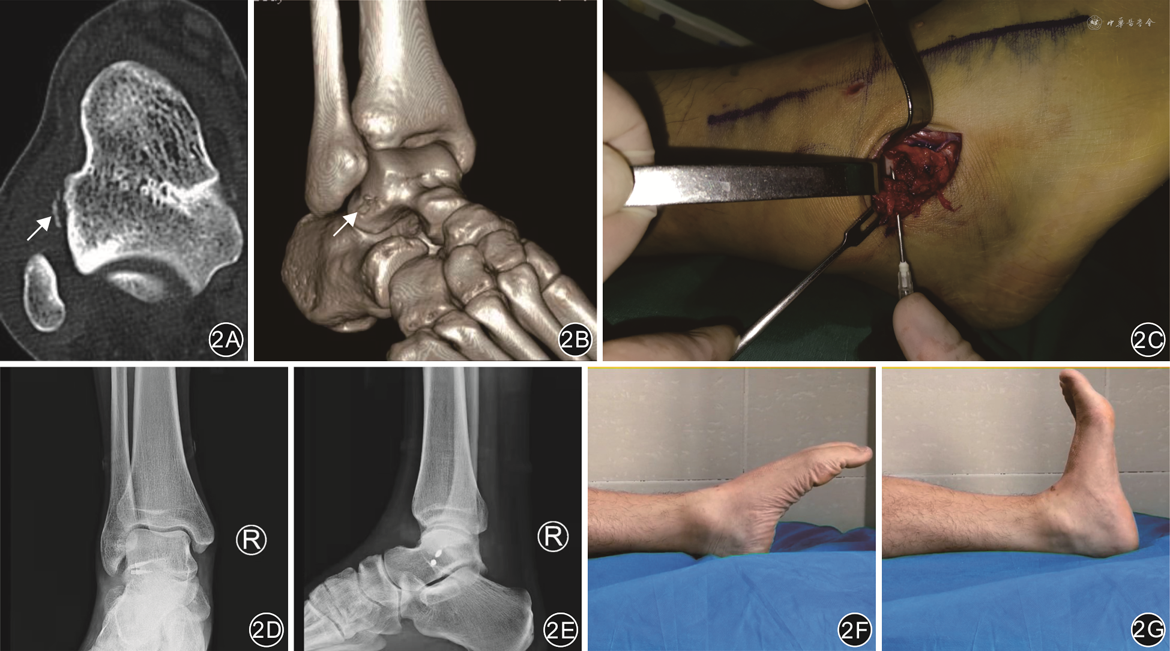

回顾性研究。纳入2017年11月—2021年4月徐州仁慈医院足踝外科4例距腓前韧带距骨侧止点撕脱骨折患者。其中,男3例,女1例;年龄15~45岁(平均30.25岁);左足2例,右足2例;运动扭伤2例,下楼扭伤1例,交通伤1例;3例患者急诊手术治疗,1例保守治疗3个月无效转手术治疗。患者术前均有外踝前下方距腓前韧带(anterior talofibular ligament,ATFL)走行区压痛,麻醉下踝关节10°跖屈位前抽屉试验阳性,均行踝关节正侧位、应力位X线片及CT检查。4例患者均采用小切口开放手术治疗距腓前韧带距骨侧损伤,手术均由同一高年资足踝外科医师完成。

患者取仰卧位,采用椎管内麻醉联合神经阻滞。患侧大腿根部固定止血带,充气加压至50 kPa。以距骨外侧撕脱骨块定位为中心,于外踝前外侧做2.5~3.0 cm弧形手术切口,依次切开皮肤、皮下组织,皮下分离时注意保护腓浅神经外侧支。沿距腓前韧带走向暴露至距骨侧止点,见距腓前韧带距骨侧止点连带部分骨皮质完全撕脱,将踝关节内翻暴露出撕脱骨折块,清理断端淤血,大量生理盐水冲洗切口。选择2枚2.8 mm金属锚钉(上海凯利台医疗科技公司,T418型)固定,定位进针点为距骨侧距腓前韧带止点处,电钻钻孔,置入金属锚定,1枚打向内上方,1枚水平位置入。术中根据距腓前韧带距骨侧止点撕脱骨折块大小,选择固定材料,缝合复位固定骨折块,将韧带缝合加强。缝合牢靠后,术中C臂X线机透视确认锚钉位置满意,检查踝关节已稳定。常规缝合,加压包扎。踝关节石膏固定于轻度外翻位。

4例患者手术均顺利完成。术后均获随访8~25个月(平均16个月)。切口均一期愈合,踝关节肿痛明显缓解,患者均未出现线结反应、感觉过敏等并发症,踝关节前抽屉实验均阴性,行走步态如常。4例患者骨折愈合良好,愈合时间3~5个月,平均3.8个月。

末次随访AOFAS踝-后足评分为89~95分(平均92.8分),Karlsson-Peterson评分为89~94分(平均91.5分)。

末次随访时ATT为(2.4±0.3)mm、TT为2.8°±0.8°,较术前的(8.4±0.8)mm、10.0°±1.4°有改善,差异均有统计学意义(t=14.40、19.62,P值均<0.001)。

对手术时机的选择,冯仕明等[17]利用踝关节镜对距腓前韧带损伤患者早期进行修复,术后结果良好。本研究中有3例患者急诊入院手术治疗,通过早期开放修复距腓前韧带在距骨侧的撕脱骨折,术后随访过程中患者疼痛明显缓解,踝关节运动水平恢复正常,骨折愈合时间3~4个月(平均3.33个月)。本组中有1例陈旧损伤患者伤后3个月来院,术中见骨折端增生硬化,清理骨折断端硬化骨至出血,使其表面新鲜化再行复位,患者的后期愈合良好,愈合时间约5个月,较其余3例新鲜骨折的患者稍长;但是1例陈旧性损伤病例不具代表性,对于手术时机的选择还需要大量的病例研究来论证。

本组4例患者均采用踝关节前外侧小切口结合置入锚钉的方式修复距腓前韧带在距骨侧止点的损伤,切口小、暴露充分,利于手术操作,术中直视下解剖复位撕脱的距骨骨块并修复受损韧带,同时避免了损伤腓浅神经。术后4例患者的踝部切口均一期愈合,无皮肤软组织感染、线结反应等并发症,早期行功能锻炼,踝关节活动度恢复基本正常,前抽屉实验阴性,行走步态如常;末次随访AOFAS踝-后足评分及Karlsson-Peterson评分均显示疗效满意,ATT和TT较术前改善。